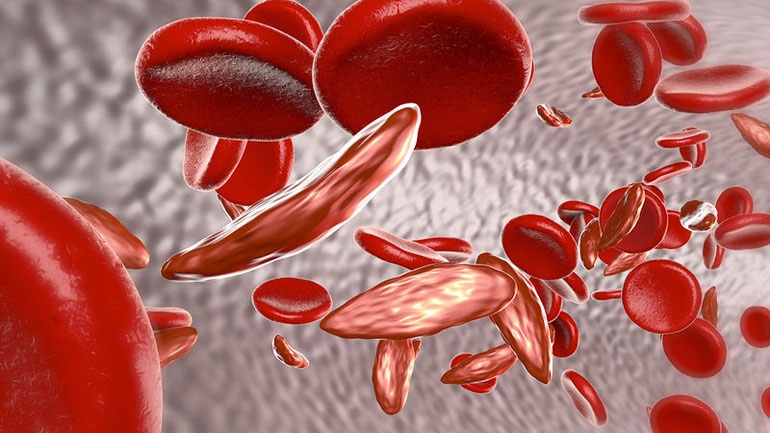

Κινήσου ενάντια στη θρόμβωση

Το μήνυμα «Κινήσου ενάντια στη θρόμβωση» ήταν το κεντρικό μήνυμα όλων των ομιλητών κατά τη διάρκεια Συνέντευξης Τύπου που οργάνωσε το Ι.Μ.Ε.Θ.Α., με αφορμή τον εορτασμό της Παγκόσμιας Ημέρας Θρόμβωσης (13 Οκτωβρίου). Ο εορτασμός της Παγκόσμιας Ημέρας Θρόμβωσης που φέτος κλείνει τα 10 χρόνια, έχει την επιστημονική αρωγή 19 Επιστημονικών Εταιρειών που σχετίζονται με τη […]